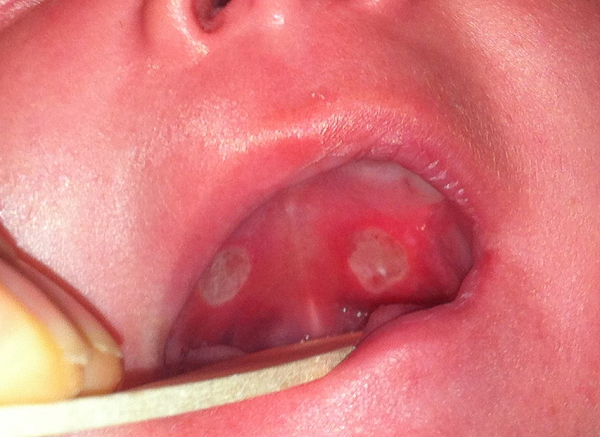

Las úlceras de Bednar, también llamadas úlceras pterigoideas1, son lesiones localizadas en el tercio posterior del paladar, con un halo hiperémico y con cobertura de fibrina, que suelen ser bilaterales, simétricas, con tendencia a confluir1-4. Pueden presentar exudado grisáceo o serosanguinolento2,3 (Figura 1).

Figura 1. Úlceras de Bednar bilaterales. Mostrar/ocultar